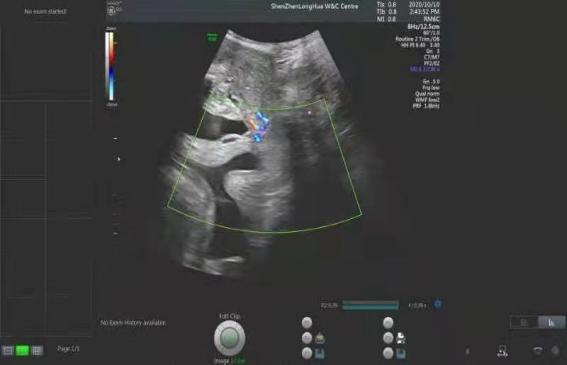

无痛人流 > 正文 5,术前需b超确定胚胎位置,大小,排除宫外孕,葡萄胎等

孕5月胎儿位置示意图

孕中期胎儿位置示意图

怀孕五个月子宫位置图

怀孕五个月胎儿彩超